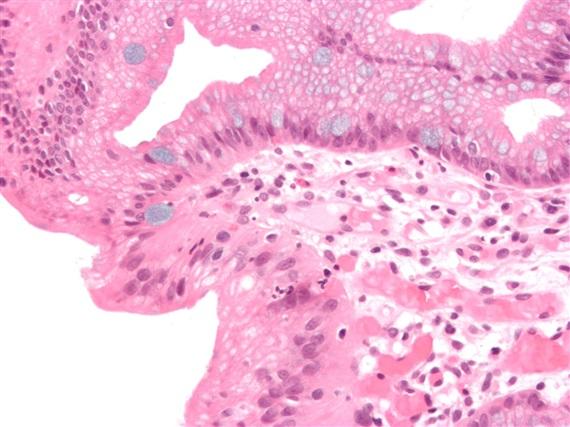

The changes are easily seen under a microscope. The inner lining of the digestive tract is made up of cells known as epithelial cells. In the esophagus, they take the form of squamous, or stratified, cells, which are layered horizontally, like bricks in a wall. In the intestine, they’re known as columnar cells, which resemble bricks stacked vertically. Stratified cells have a protective function, preventing harmful substances from coming in contact with underlying cells; columnar cells absorb nutrients from food. In people with Barrett’s esophagus, cells at the intersection of the esophagus and stomach, which should appear stratified, look exactly like columnar, intestinal cells.